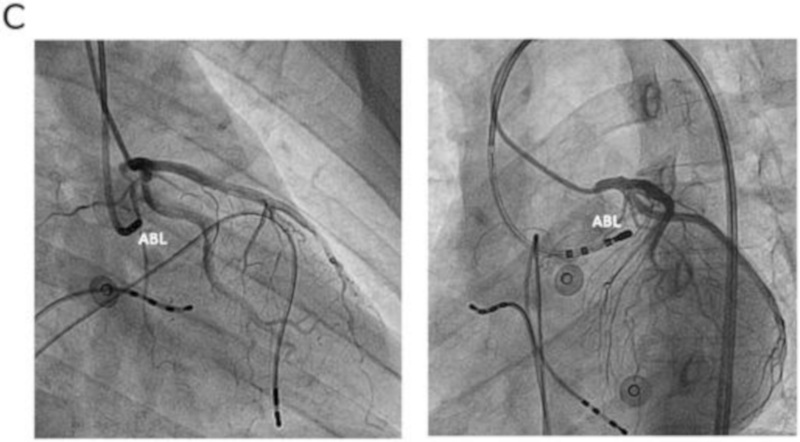

Ablation in coronary cusps - Aware of relationship to coronaries

cor_angio.jpg